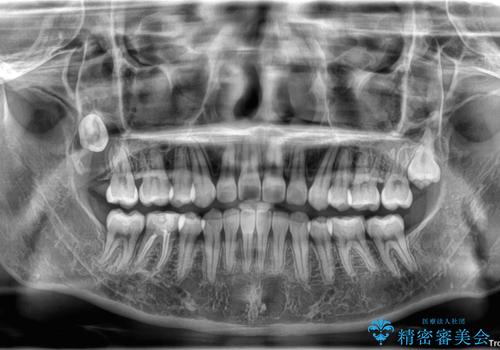

転勤でも安心して治療継続 抜歯スペース閉鎖と深い噛み合わせ改善のワイヤー矯正

- 転勤により東京へ移られることになり転院先を探されていた患者様です。ワイヤー矯正の途中での急な転勤なうえ、今後2~3年以内に再度転勤になる可能性もあるというご事情でした。

そのため、限られた期間内に効率よく治療を完了するために、「抜歯スペースの確実な閉鎖」「深い噛み合わせ(過蓋咬合)の改善」の2点を主軸とした治療計画を立てました。

結果的に1年半で、再度転勤になる前に治療を終えることができました。